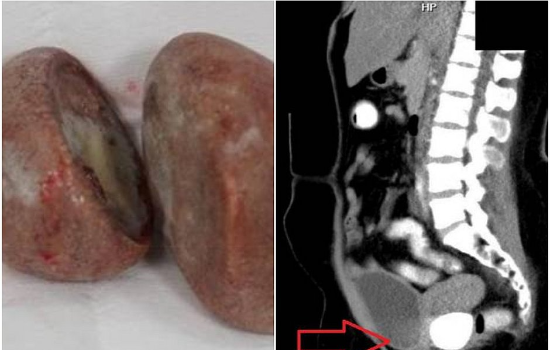

Imagens impressionantes publicadas nesta semana na revista "Urology Case Reports" mostram as pedras do tamanho da palma da mão que foram removidas do corpo de uma paciente indonésia após uma cirurgia.

Um exame simples, porém, levantou sinais de que algo estava obstruindo a vagina. Exames de imagem mostraram duas pedras "sólidas e lisas" dentro da área pélvica.

Medindo 3,6cm por 5cm e 5cm por 5,8cm, as pedras retiradas eram do tamanho de duas bolas de pingue-pongue. Uma estava presa à parede da bexiga, enquanto a outro estava presa à parede do reto.